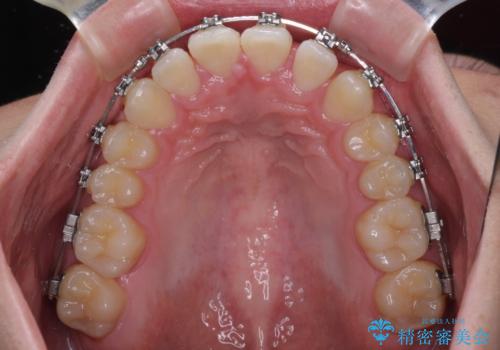

- メタルブラケット

- 1年1ヶ月

ワイヤー矯正でもインビザライン矯正でも対応可能でしたが、インビザラインでの自己管理の煩わしさを避けるため、ワイヤー装置にて矯正治療を行うこととしました。

傾斜しいている大臼歯を立ち上げながら、下顎歯列を上顎に対して前方位となるように工夫し、デコボコを解消した上でディープバイトも改善することができました。